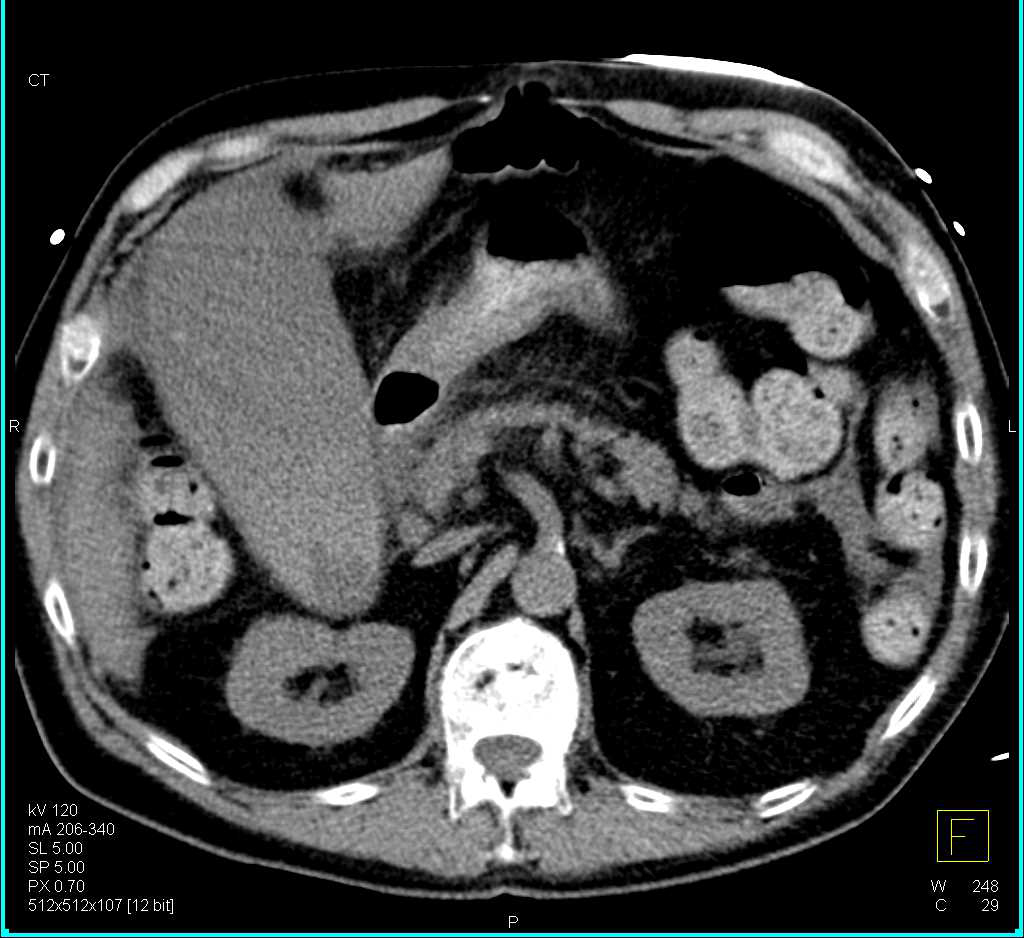

Gastrointestinal (GI) Bleed due to Rectal Varices in a Patient with Portal Hypertension